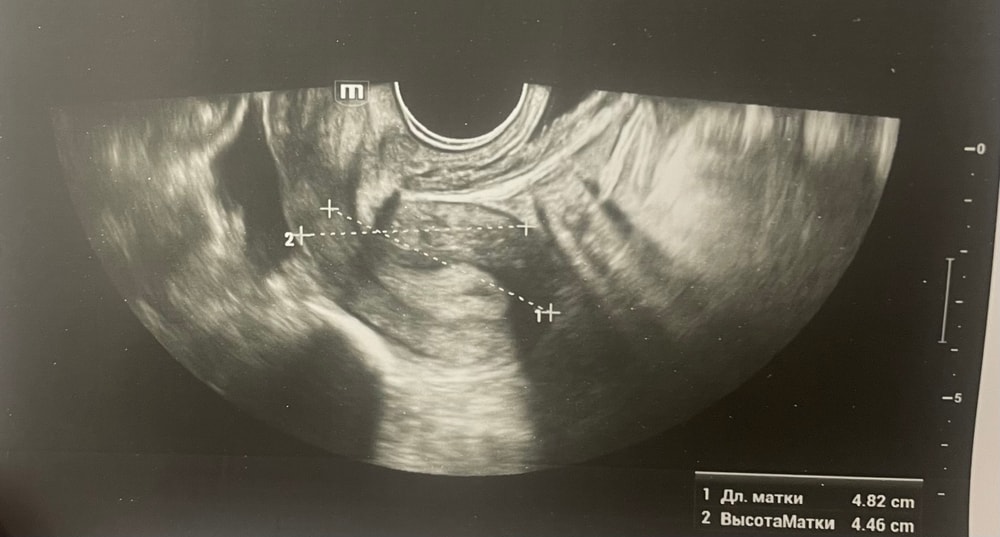

УЗИДобрый день, мы с мужем планируем беременность и в этом месяце произошло что то странное… дата начала последней менструации 4 октября закончилась 8, овуляцию отслеживала всю неделю почти сначала были бледные еле заметные полоски, 23 октября жирные четкие полоски, 24 октября стала чуть бледнее но яркая, вообщем положительный ещё был, с 25 числа тест уже отрицательный, через день после овуляции 26 числа стала странно себя чувствовать и во время овуляции болел живот то справа то с лева и поясница, так через день после начали болеть соски грудь вообще не болела, живот то болит то нет и с поясницей также, позже появилась небольшая изжога, нога немеет правая не знаю с чем связано), все это началось за 2 недели до месячных в середине цикла скажем так 29 числа пошла на узи спустя 6 дней грубо говоря гиня сказала что у меня была очень хорошая овуляция, что её признаки сохраняются до сих пор так скажем, желтое тело СПРАВО 20 мм, мои симптомы и все это очень похоже на беременность сказали большая вероятность, я очень была рада и надеялась, после узи появились выделения с комочками, до этого были просто густые белые выделения, утром тоже самое, пошла опять к гинекологу она сказала это может быть при ранец беременности сказала какие свечи купить, вечером я попала в не большое ДТП, удар был в поясницу и копчик, живот начал тянуть и поясница сильно болеть, начала болеть сама грудь помимо сосков, живот прошел относительно быстро, а вот поясница ломит до сих пор, решила сходить ещё раз на узи очень испугалась, на узи я пошла 31 через два дня после предыдущего и уже к другому гинекологу, моя на больничном, она сказала, что у меня отсутствуют даже косвенные признаки беременности и желтое тело с ЛЕВО А НЕ С ПРАВО, я не понимаю как такое может быть, очень расстроилась и совсем забыла про фото узи, она мне его не дала только заключение и как выяснилось уже не дадут оно не сохранилось, сказали переделывать, я очень доверяю своему гинекологу, но по заключению второго врача о беременности не может быть и речи в этом цикле, я не понимаю как желтое тело оказалось с лево если оно точно было справа в этом я уверена, а вторая врач уверяет во Братном, живот в обуляцию хоть и болел с двух сторон но больше справа помойму, вообщем я не понимаю есть ли шанс что я беременна или все таки нет, я понимаю что это слишком рано, до задержки ещё 4 дня, но мне плохо уже неделю по симптомам даже больше это же не просто так, я прикреплю фото заключения, могу ли я быть беременна, если посмотреть на эти заключения хотябы, подскажите пожалуйста фото узи относятся к 29.10, без фото 31.10